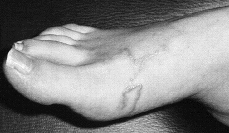

Mujer de 28 años de edad que acudió a consulta por presentar unas lesiones lineales que han ido avanzando a partir de pequeñas pápulas que presentaba en el pie derecho desde hacía 5-6 días. Las primeras lesiones aparecieron a la semana de volver de una estancia en Costa Rica. A la exploración se apreciaban estas lesiones lineales, eritematosas y serpentiformes, así como pequeñas pápulas eritematosas, ambas en dorso de pie derecho (Fig. 2).

FIG. 2.--Caso 2. Lesiones serpiginosas elevadas en doso y cara lateral del pie.